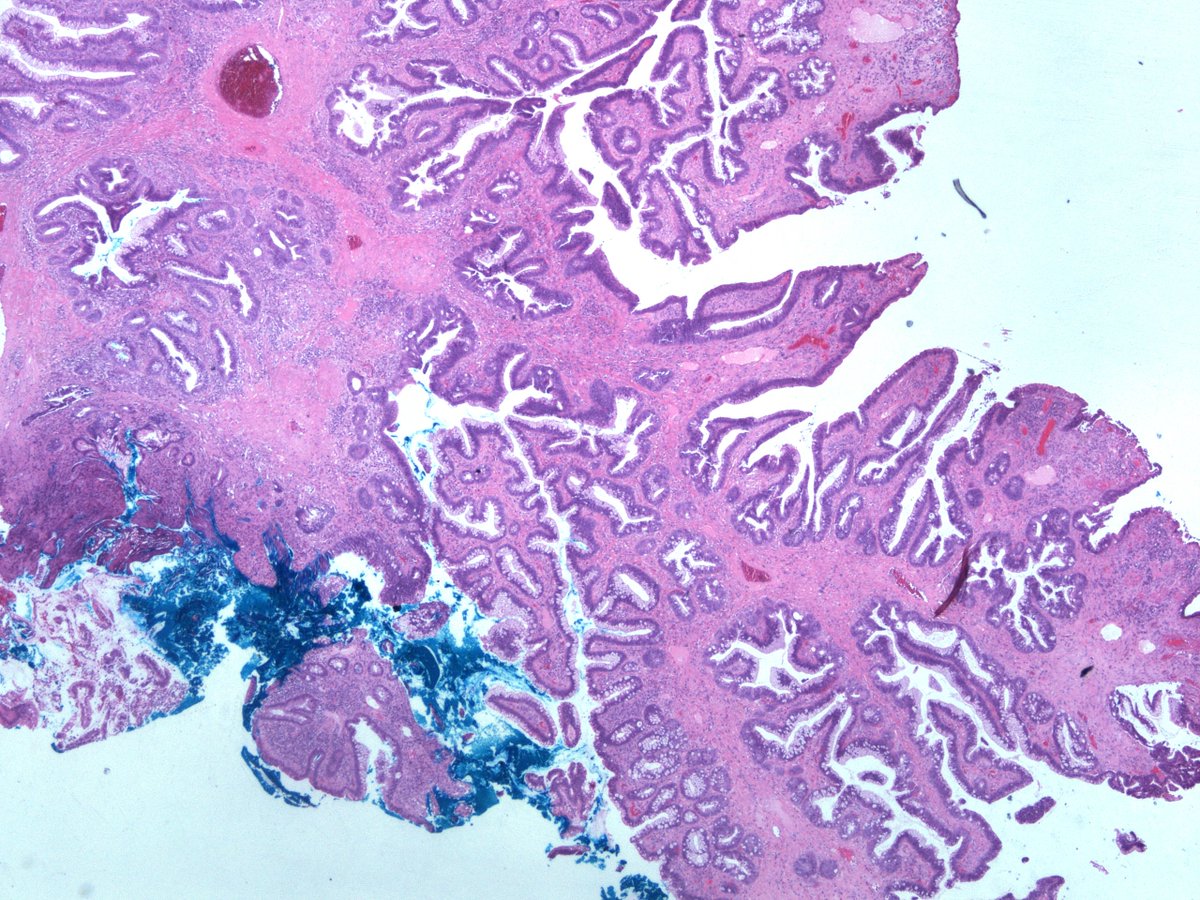

Dear Tweeples, help please. 20mm polyp in sigmoid colon in a background of longstanding mildly active IBD . Is it DALM? Is it Sporadic adenoma? How would you grade it? Any ancillary tests that may add value ? #GIpath #pathologyresidents .more images. @RunjanChetty @MAHoureih